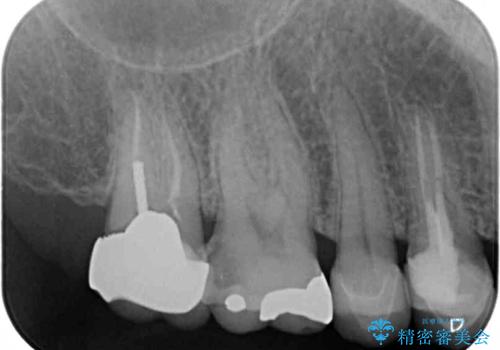

- 奥歯の間にものが挟まって不快であるとのことで来院された患者様です。

検査を行った結果、非常に強い咬合力により隣の歯との隣接面にひびが入り、虫歯が拡大している状態でした。

部分的にゴールドインレーが装着されていたので、虫歯と合わせて除去し、新たにゴールドインレーにて修復治療を行うこととしました。